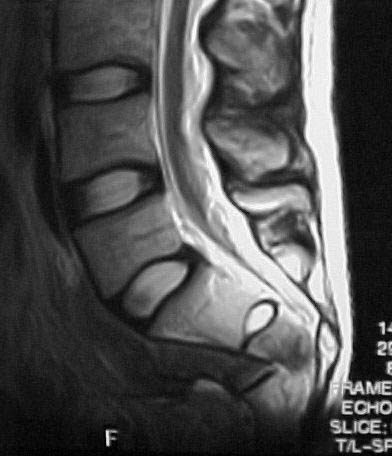

A 28 year old male jumped from the 4th floor on 11-25-2000 sustaining an L1 burst fracture that has been fixed anteriorly by the neurosurgeon with a strut between T12 and L2. A Kaneda device was placed anteriorly as well. My concern is the pelvic ring injury. There are bilateral sacral fractures through the foramen and a transverse element through the sacrum between S2 and S3. the lower part of the sacrum is displaced forward. Anteriorly there are right superior and inferior pubic rami fractures.

Sagittal

Thanks for educating me about this lesion. I'm sure that I have missed a couple in my career. I won't miss any more. The concept of the spine disconnecting from the pelvis is wonderful. The concept of the spine going posterior rather than thinking of the distal sacrum as going anterior helps conceptualize the real pathology. Kind of like AC joint separations where the shoulder drops down rather the clavicle going up.